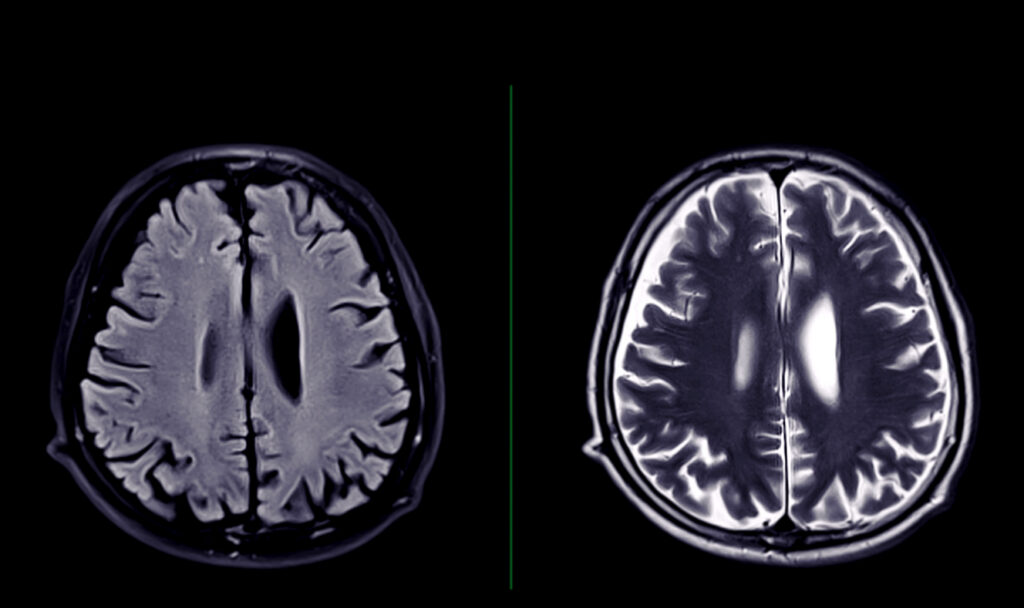

Since CTE is rare, there is still a lot that experts don’t know about it. There is no known cure, and it can’t be diagnosed during a person’s lifetime. Tools such as an MRI or CT scan can’t detect CTE.